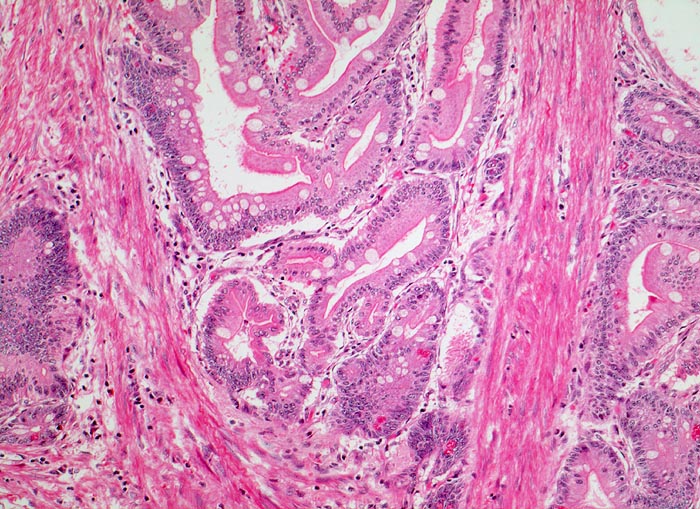

AP/ Peutz-Jeghers Polyp, Dünndarm

Peutz-Jeghers Polyp, Dünndarm

Diagnose Gruppe

Topographie Gruppe

Jejunum